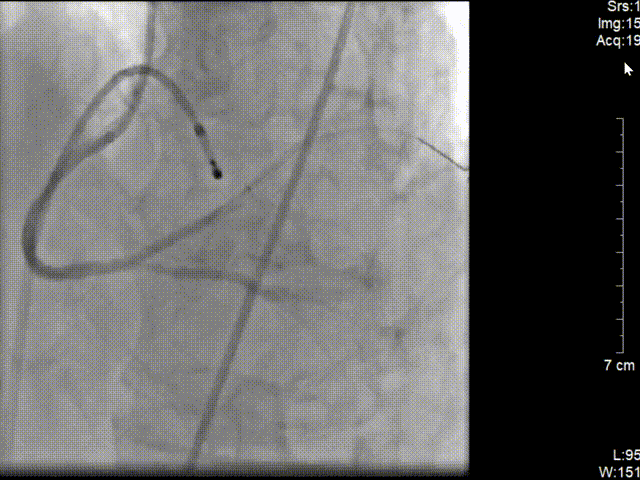

右图:右冠远段、近段各植入药物支架1枚。

再次予2.0*15预扩张球囊行病变处预扩张处理,右冠近中置入3.5*40mm药物支架1枚,继续予以3.5*15m后扩张球囊行支架内优化扩张。

复查造影可见右冠远段狭窄80%,并见血栓,予2.0*15预扩张球行右冠远段病变处预扩张,于右冠远段置入2.5*14mm 药物支架1枚,并予以3.0*12mm后扩张球囊行支架内扩张优化。再次造影示右冠狭窄消失,无夹层及残余狭窄,TIMI血流3级。